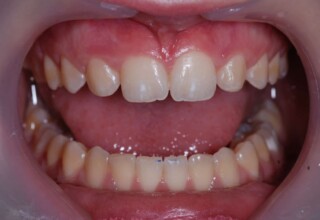

Δυσχρωμικοί άνω πλάγιοι τομείς

Αρχική εμφάνιση

Τελική εμφάνιση